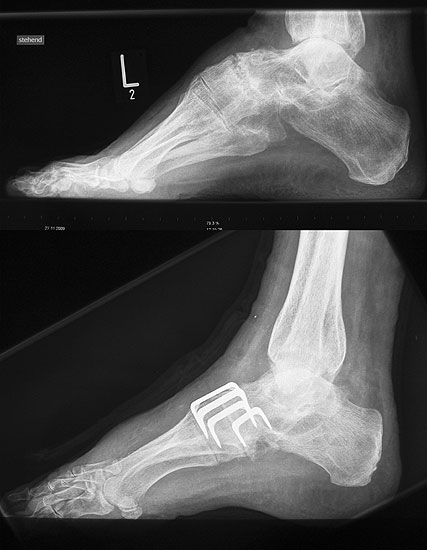

Lateralisierende Calcaneus-Osteotomie (Abb. 2 und 3, Video 2)

Die lateralisierende Calcaneus-Osteotomie ist ein Standard-Operationsschritt bei fast jeder Hohlfuβkorrektur. Der biomechanische Effekt der Osteotomie ist eine Verschiebung des Fersenkontaktpunktes und damit der beim Rückfuβ varus medialisierten Belastungsachse durch das OSG nach lateral. Diese statische Rückfuβ-Korrektur allein ist in der Lage, den bei Pes cavovarus anteromedial erhöhten OSG-Druck, der sehr wahrscheinlich zur korrespondierenden Arthrose führt, zu neutralisieren 7. Zuklappende Osteotomien mit Entnahme eines lateralen Knochenkeils haben sich dabei weniger effektiv gezeigt als solche mit Lateralisation des Tubers. Mit der Lateralisation des Achilles-Ansatzes verringert sich die Inversionskraft der Sehne zugunsten der schwachen Eversion, wodurch gleichzeitig die Prädisposition für Supinationstraumata reduziert wird. Neben der klassischen Dwyer-Osteotomie (Entnahme eines lateralen, vertikalen Keils 8 haben sich vor allem die technisch einfache Verschiebe-Osteotomien („sliding osteotomy“) und die Z-förmigen Osteotomien (Pisani 1993, Malerba 9) mit Entnahme eines lateralen Keils aus dem horizontalen Anteil der Osteotomie aber ohne Lateralisation des Tuberfragmentes, sowie die Korrektur nach Hintermann (Knupp 2008) mit zusätzlicher Lateralisation des Tuberfragmentes) durchgesetzt. Bei neutral aligniertem OSG ist keine supramalleoläre Tibia-Osteotomie zur Korrektur des Rückfuβ varus indiziert. Generell sollten Osteotomien gegenüber korrigierenden Arthrodesen der Vorzug gegeben werden. Die im Folgenden beschriebene Verschiebeosteotomie ist technisch einfach und hinsichtlich OSG-Druckneutralisation ebenso effektiv wie die Z-Osteotomien 7.

• Umfahren des Calcaneus mit Hohmann Hebeln und Markieren der Osteotomie mit 2 1.6 Kirschnerdrähten; Kontrolle der korrekten Osteotomie-Ebene im BV, diese sollten, da in der Regel keine Verkürzung oder Verlängerung des Rückfuβes gewünscht ist, in der axialen Projektion genau rechtwinklig zur Achse des Calcaneus verlaufen; seitlich beginnt die Osteotomie proximal etwa 2 cm anterior des Achilles-Ansatzes und läuft etwas schräg nach distal-anterior.

• Sägen der Osteotomie mit vorsichtigem Eröffnen der medialen Kortikalis, um die dortigen neurovaskulären Strukturen zu schützen (evtl. palpierenden Finger gegenhalten) (Abb. 2).

• Kontrolle der korrekten Schraubenlage im BV (Abb. 3).